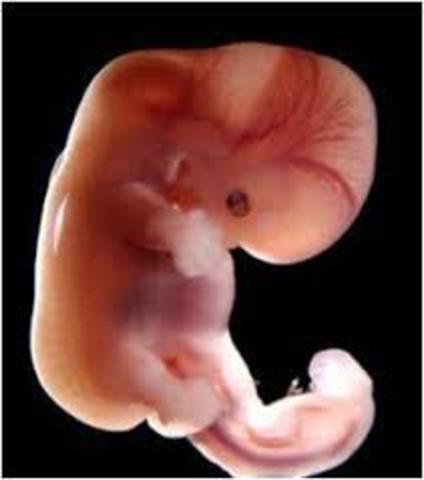

• semana 2 de embarazo

semana 2 de embarazo

El embarazo se mide en semanas a partir de la última regla, pero el bebé se concibe antes. A partir de la semana 2 del embarazo, se desarrolla lo que llamamos embrión, que tiene básicamente una cabeza, un tronco y una cola rizada. Las primeras semanas de embarazo son muy importantes porque, aunque todavía es un embrión, empieza a desarrollar los cimientos de lo que serán sus órganos, sus rasgos y su sistema nervioso.